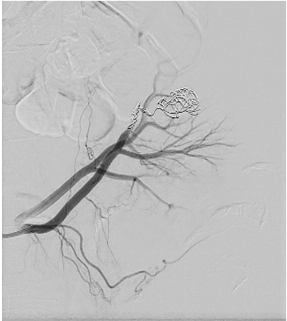

Control angiography with contrast was performed. Pseudoaneurysm was completely occluded and no longer visible (Figure 6). No extravasation was found.

After embolization, creatinine decreased till 83 µmoL/L and eGFR was 73 mL/min/1.73 m2. Pseudoaneurysm was no longer visible, as well as small segmental branches. Vascularization of renal parenchyma is reduced.